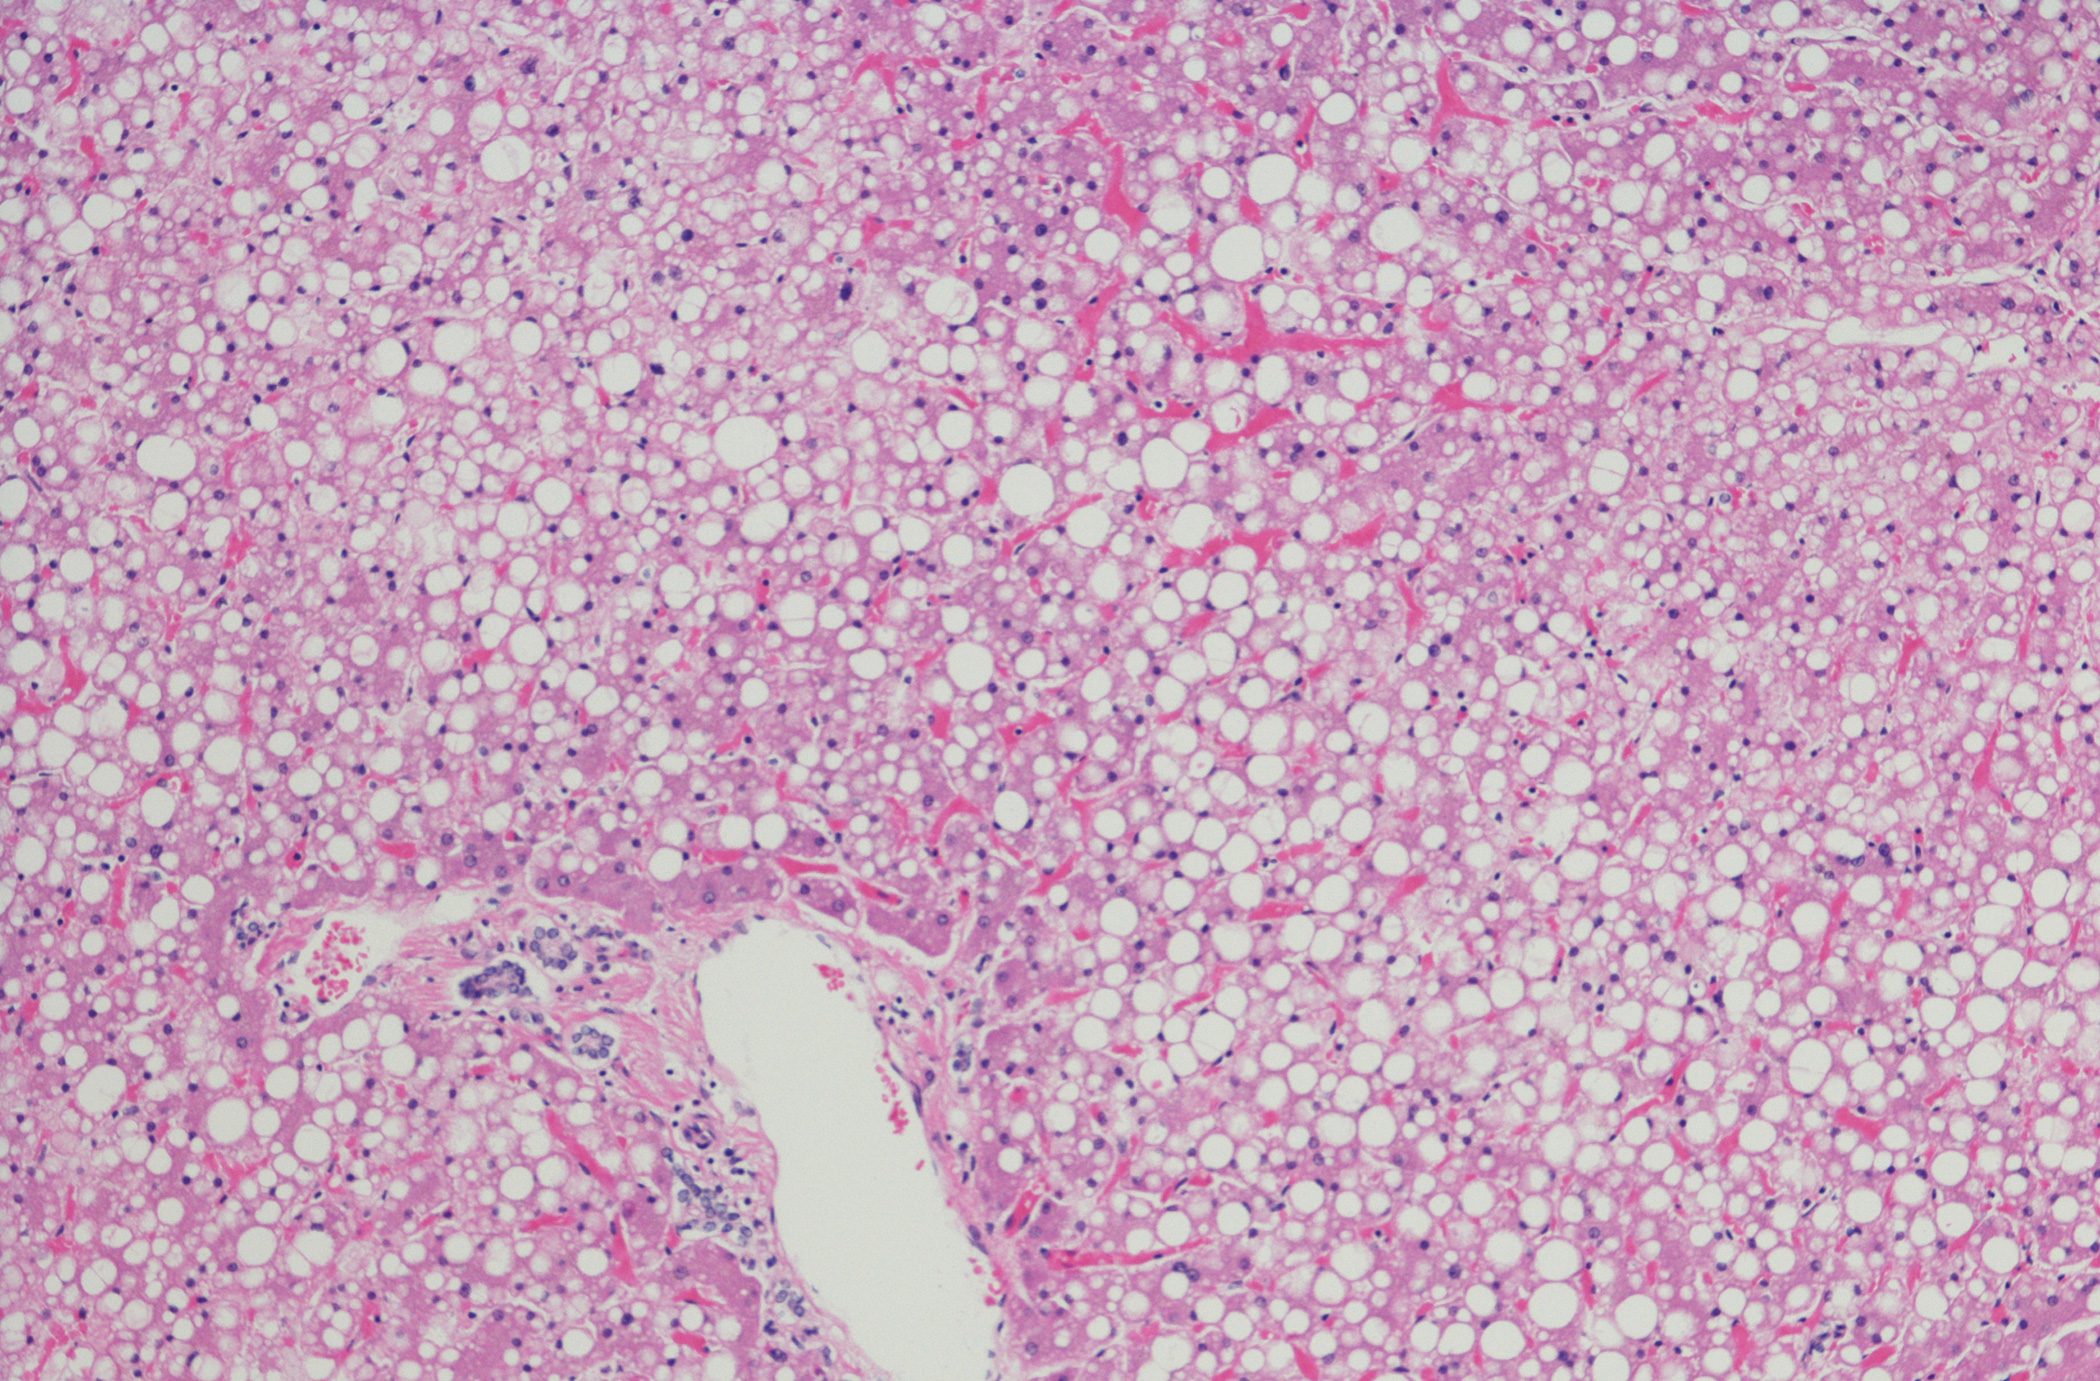

• Steatotische Lebererkrankung

GLP-1RA bei MASH – was gibt es Neues?